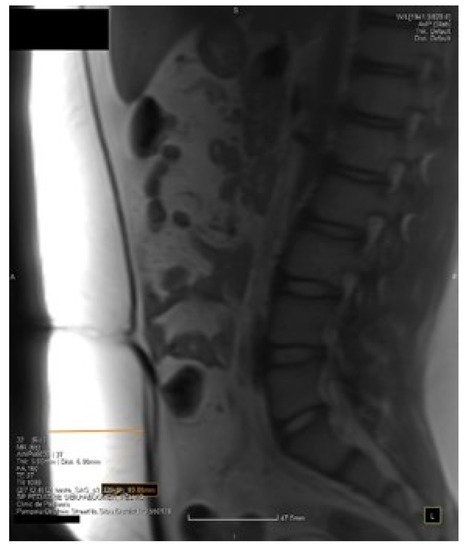

- Shen, W.; Liu, H.; Punyanitya, M.; Chen, J.; Heymsfield, S.B. Pediatric obesity phenotyping by magnetic resonance methods. Curr. Opin. Clin. Nutr. Metab. Care 2005, 8, 595. [Google Scholar]

- Shen, W.; Chen, J.; Gantz, M.; Velasquez, G.; Punyanitya, M.; Heymsfield, S.B. A single MRI slice does not accurately predict visceral and subcutaneous adipose tissue changes during weight loss. Obesity 2012, 20, 2458–2463. [Google Scholar] [CrossRef] [PubMed]

- Samara, A.; Ventura, E.; Alfadda, A.; Goran, M. Use of MRI and CT for fat imaging in children and youth: What have we learned about obesity, fat distribution and metabolic disease risk? Obes. Rev. 2012, 13, 723–732. [Google Scholar] [CrossRef]

- Takatalo, J.; Karppinen, J.; Taimela, S.; Niinimäki, J.; Laitinen, J.; Sequeiros, R.B.; Samartzis, D.; Korpelainen, R.; Näyhä, S.; Remes, J.; et al. Association of abdominal obesity with lumbar disc degeneration—a magnetic resonance imaging study. PLoS ONE 2013, 8, e56244. [Google Scholar] [CrossRef]

- Eloi, J.C.; Epifanio, M.; de Gonçalves, M.M.; Pellicioli, A.; Vieira, P.F.; Dias, H.B.; Bruscato, N.; Soder, R.B.; Santana, J.C.; Mouzaki, M.; et al. Quantification of Abdominal Fat in Obese and Healthy Adolescents Using 3 Tesla Magnetic Resonance Imaging and Free Software for Image Analysis. PLoS ONE 2017, 12, e0167625. [Google Scholar] [CrossRef]